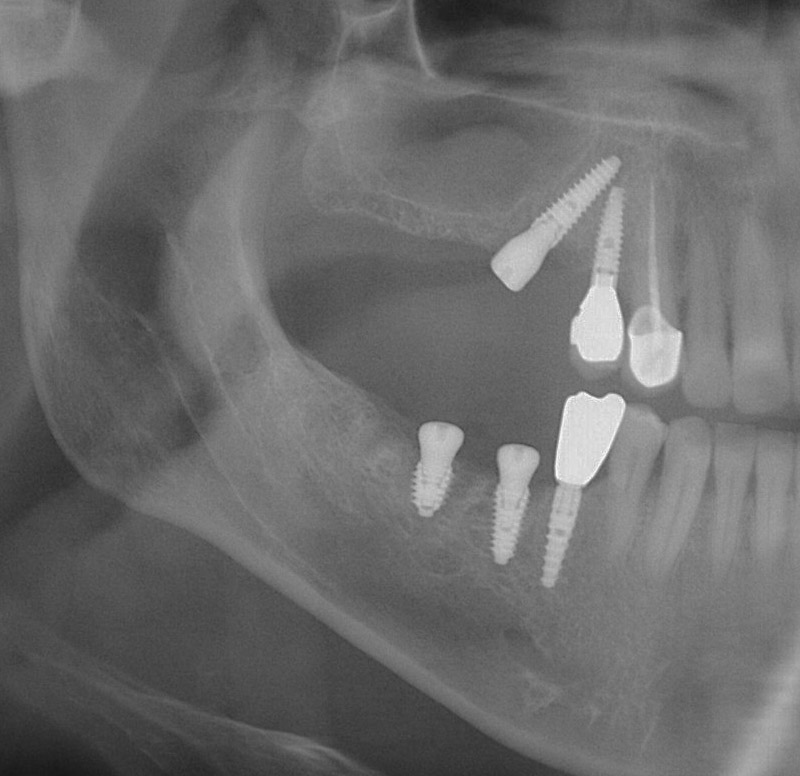

Під час стоматологічного обстеження лікар оцінює стан порожнини рота, зубних рядів, слизової оболонки, прикусу, проводить рентгенологічне дослідження, визначає можливість імплантації та її конкретний вигляд. Крім того, при необхідності, наприклад, у тих випадках, коли є хронічні захворювання, які потребують контролю, або пацієнт приймає певні препарати, проводиться низка досліджень, які допомагають оцінити загальний стан організму. Для цього виконуються аналізи крові та сечі, ЕКГ, а також консультація терапевта чи сімейного лікаря.

Виконує операцію на віртуальній моделі з оцінкою будови та товщини кістки, а також можливості встановлення імплантату. Імпланти підбираються індивідуально для кожного пацієнта, залежно від клінічної ситуації та завдання.

Абсолютно безболісно встановлюється імплантат у правильну позицію завдяки сучасним апаратам сканування 3 Д діагностики з подальшим виготовленням шаблону для імплангтації.